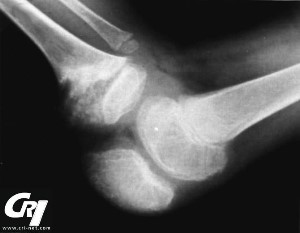

cri-net.com

Articular (joint) affects are present in variable degrees in most patients with NOMID/ CINCA. Periodic swelling without damage between flare-ups of inflammation are generally present. There can also be disfiguring and uncontrolled anomalous changes to the growth cartilage, often at the knees, suggestive of a pseudo-tumor growth. Many people that have developed this have enormously enlarged kneecaps (patellas) and other bony overgrowth at the large joints. This can occur in approximately 50% of people with NOMID. Often, biopsy findings show disorganized cartilage with no inflammatory cells present.

In the past, physicians thought that the enlarged, bony overgrowth was a necessary characteristic in order to diagnose someone with NOMID/CINCA, but now it is known that not all people with this syndrome develop the irreversible, disfiguring and debilitating damage to the joints. There is a great degree of variance in inflammation, deformity and pain in the joints with NOMID/CINCA.